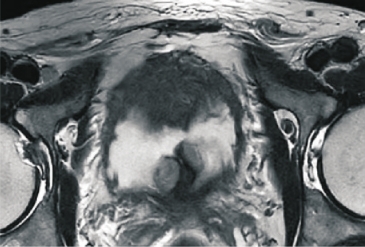

该患者不能自主排尿一周,检查发现血清前列腺特异性抗原水平升高,达到17.45ng/ml,多参数磁共振检查提示前列腺外周带右侧叶结节,PI-RADS评分4分。首先进行了前列腺穿刺活检,病房目前采用的是“磁共振超声融合,靶向加模板”无痛活检技术。在穿刺前将磁共振检查中确定的可疑病灶进行精准定位,然后有针对性地进行靶向活检,同时结合模板活检方法对整个前列腺腺体进行标准分区,每个分区内获取一针活检标本,并进行病理分析,不但可以确定前列腺内是否存在肿瘤,而且可以准确了解病灶的部位及范围,为后续的精准治疗奠定基础。病理报告为前列腺癌。